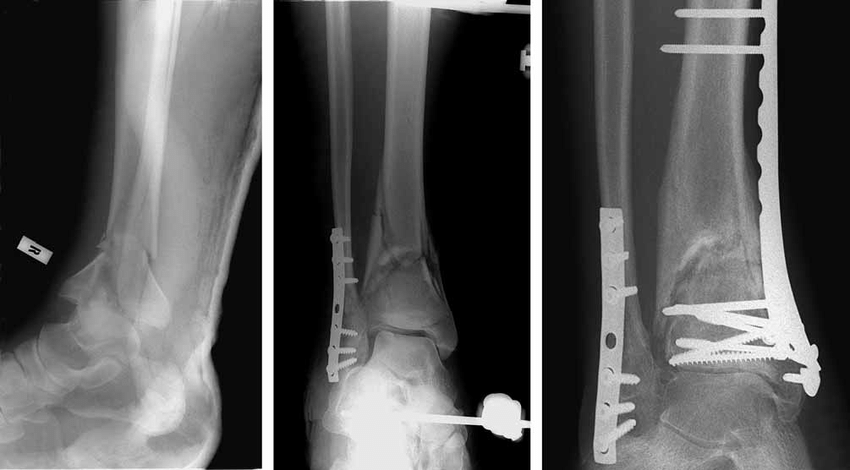

Çoğu Pilon Tipi Tibia Distal Domen Sendromu vakasında, cerrahi müdahale kaçınılmazdır. Cerrahi tedavi, kırık parçalarının anatomik olarak doğru bir şekilde yerleştirilmesini ve eklem yüzeyinin yeniden yapılandırılmasını içerir. Açık redüksiyon ve internal fiksasyon (ORIF), en sık kullanılan cerrahi yöntemdir. Bu yöntemde, kırık kemikler plaklar ve vidalarla sabitlenir. Ayrıca, ciddi yumuşak doku hasarı varsa, cerrahi öncesi bir süre eksternal fiksatör kullanımı gerekebilir. Doç. Dr. Ramadan ÖZMANEVRA, cerrahi sonrası rehabilitasyon sürecinin, tedavi başarısında en az cerrahi kadar önemli olduğunu belirtmektedir.